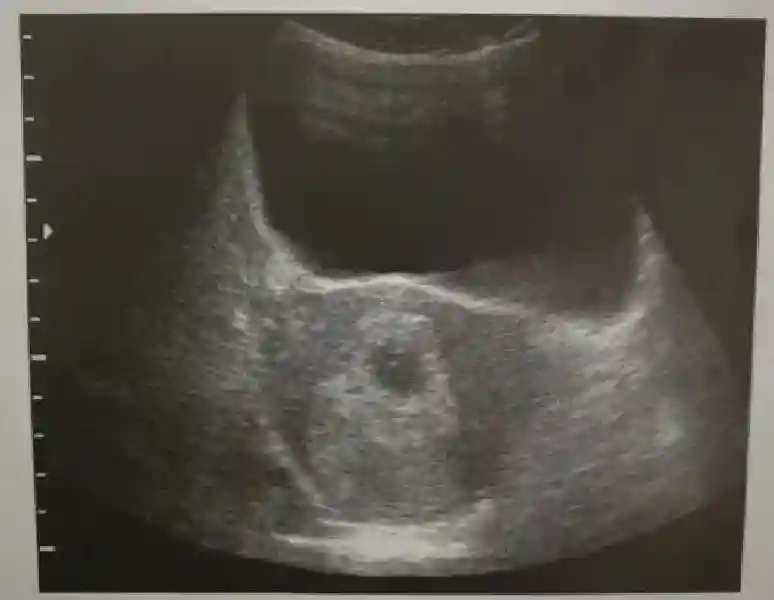

1??妊娠囊:早期妊娠囊:正常妊娠囊位于宮腔上段,表現(xiàn)為宮腔內(nèi)圓形或橢圓形的無(wú)回聲區(qū),周邊為完整的、厚度均勻的強(qiáng)回聲環(huán),強(qiáng)回聲環(huán)厚度≥2mm,強(qiáng)回聲是妊娠絨毛的回聲,隨著妊娠囊的增大,形成特征性的“雙環(huán)征” ,10周以后消失。正常的妊娠囊增長(zhǎng)速度是平均 1 mm /d。